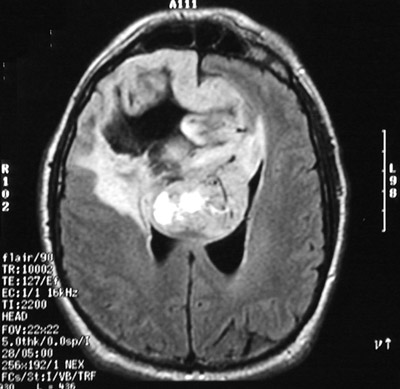

| This T2 weighted fast spin echo MRI scan above in axial view demonstrates a large glioblastoma multiforme involving much of the right cerebral hemisphere. The tumor is variegated and has central necrosis and an irregular border. It crosses the midline via the corpus callosum. The view below is a T2 weighted FLAIR image. |